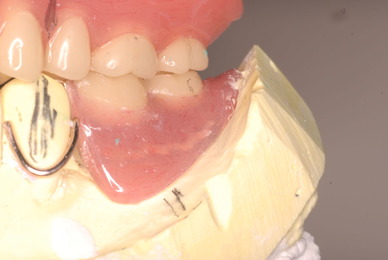

下顎です。

上の総義歯はまっったくはずれませんでした。下顎の入れ歯では若干痛みが出そうなので噛み合わせの調整をしています。口腔内では時間がかかりすぎるので器械に付けて調整しています。

下顎が右にシフトしているので噛み合わせはとても慎重にしました。下の方が頬側にないと安定せず噛めないのです。